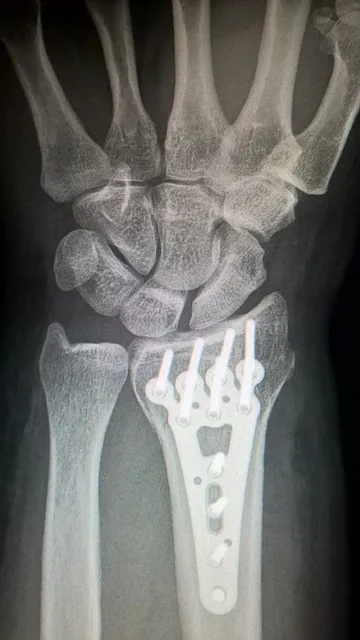

影像学检查是诊断的重要手段之一,包括X光、CT或MRI等,这些检查可以清晰地显示出内固定装置的状态及骨愈合情况。

1. **骨折愈合评估**:临床上采用影像学检查如X光片来判断骨折部位是否完全愈合。